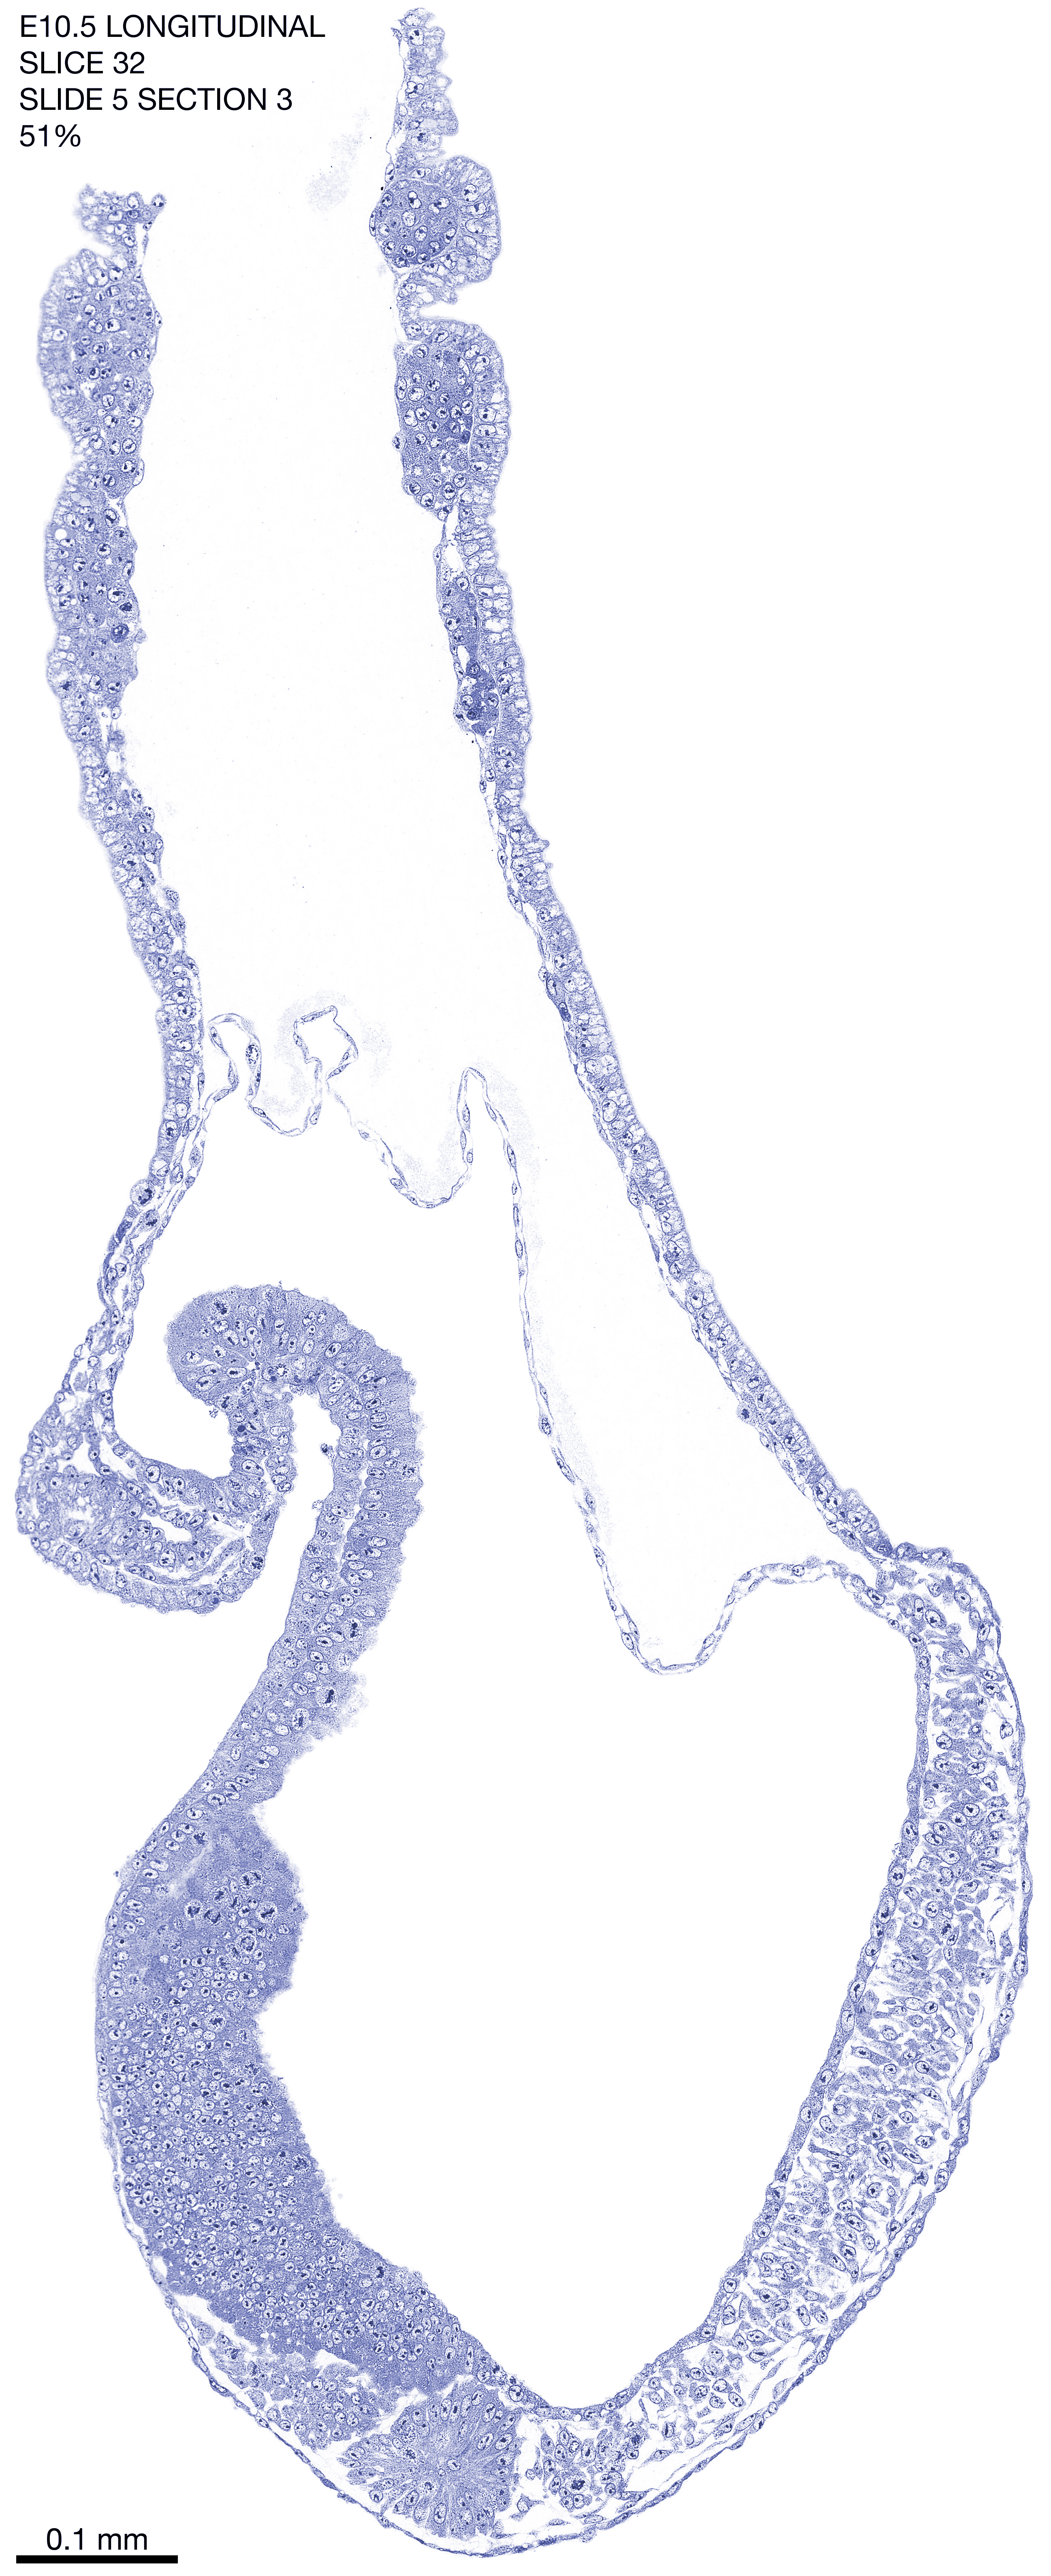

E10.5 Longitudianal Archive This page contains jpg files of ALL SLICES (each 3µm thick) that were scanned of the E10.5 longitudinally cut specimen. Download: Large | High Res Download: Large | High Res Download: Large | High Res Download: Large | High Res Download: Large | High Res Download: Large | High Res Download: Large | High Res Download: Large | High Res Download: Large | High Res Download: Large | High Res Download: Large | High Res Download: Large | High Res Download: Large | High Res Download: Large | High Res Download: Large | High Res Download: Large | High Res Download: Large | High Res Download: Large | High Res Download: Large | High Res Download: Large | High Res Download: Large | High Res Download: Large | High Res Download: Large | High Res Download: Large | High Res Download: Large | High Res Download: Large | High Res Download: Large | High Res Download: Large | High Res Download: Large | High Res Download: Large | High Res Download: Large | High Res Download: Large | High Res Download: Large | High Res Download: Large | High Res Download: Large | High Res Download: Large | High Res Download: Large | High Res Download: Large | High Res Download: Large | High Res Download: Large | High Res Download: Large | High Res Download: Large | High Res Download: Large | High Res Download: Large | High Res Download: Large | High Res Download: Large | High Res Download: Large | High Res Download: Large | High Res Download: Large | High Res Download: Large | High Res Download: Large | High Res Download: Large | High Res Download: Large | High Res Download: Large | High Res Download: Large | High Res Download: Large | High Res Download: Large | High Res Download: Large | High Res